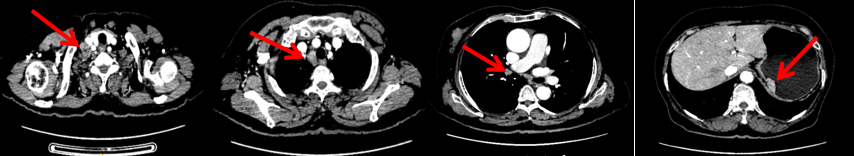

2024-11-5复查CT:右乳外上象限占位(11mm×9mm),较前明显缩小;上纵隔及右肺门多发淋巴结转移缩小;右锁骨上区淋巴结较前增大。余部位未见肿瘤转移及复发征象。

患者右锁骨上淋巴结肿大,需完善相关检查以进一步明确鳞状细胞癌的原发部位。

头颅+鼻咽部+颈部MR:右侧锁骨上区、所见上纵隔多发肿大淋巴结,考虑转移瘤。脑、鼻咽部未见明显异常。

影像科:CT显示右侧锁骨上区病灶增大主要表现为液化坏死改变,考虑为治疗后改变而非肿瘤进展所致。